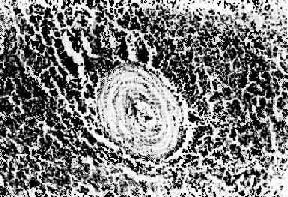

结节性多动脉炎

图4-13 结节性多动脉炎

两个动脉壁的各层都有炎性细胞浸润,外膜尤为显著。中膜发生纤维素样坏死